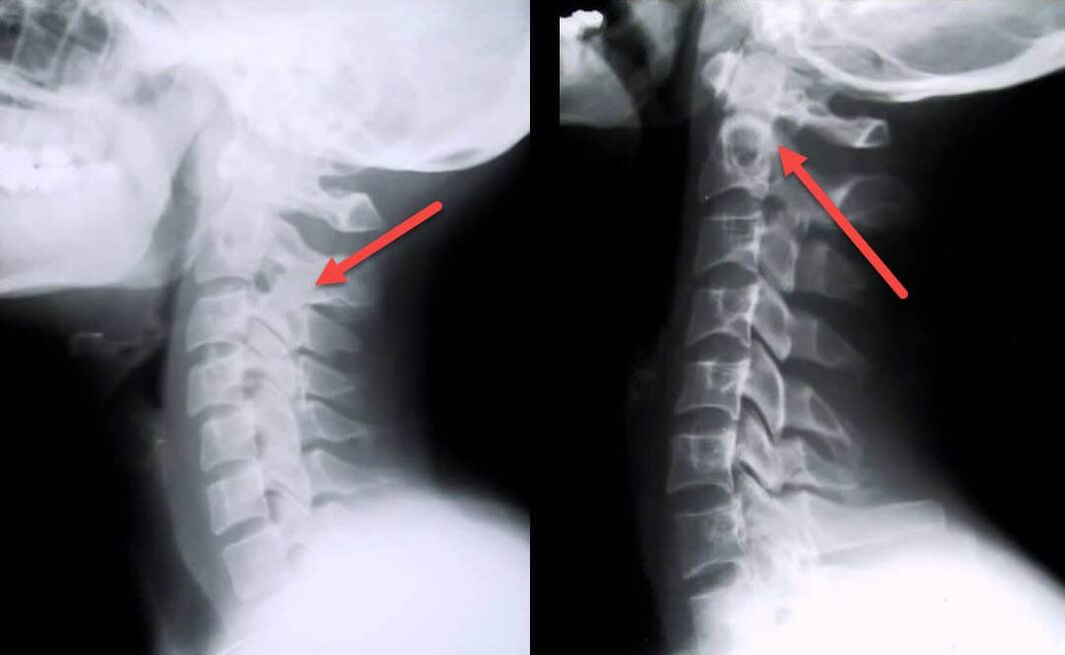

Najinformatívnejším diagnostickým postupom je rádiografia. Patológie 1. stupňa zodpovedajú 1. alebo 2. rádiologickému stupňu. Výsledné obrázky vizualizujú typické znaky ochorenia.

| Röntgenové štádiá cervikálnej osteochondrózy 1. stupňa | Charakteristické znaky |

|---|---|

| 1. fáza | Drobné zmeny v zakrivení chrbtice v krčnej oblasti, postihujúce jeden alebo viac segmentov |

| 2. fáza | Mierne zhrubnutie medzistavcových platničiek, deformácia výbežkov bez tela, napriamenie lordózy, drobné výrastky kostných štruktúr |